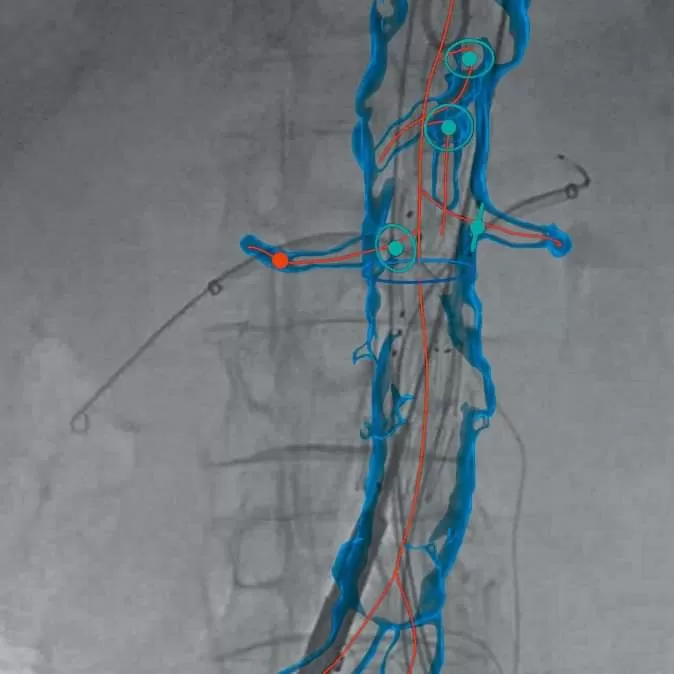

Επιτρέπουν τον εύκολο σχεδιασμό της θεραπευτικής προσέγγισης, αλλά και την ταχύτερη πλοήγηση κατά την διάρκεια ενδοαγγειακών επεμβατικών τεχνικών, με τη δυνατότητα σύντηξης εικόνων, με 3D fusion τεχνικές και προσφέρουν άμεσο έλεγχο και ταχύτητα στις ενδαγγειακές επεμβάσεις.

Το σύστημα EndoNaut συγκεκριμένα, σε συνδυασμό με ένα υψηλής τεχνολογίας ψηφιακό ακτινοσκοπικό C-arm (όπως το Ziehm Vision RFD HE) και με υψηλής ποιότητας low-dose ακτινοσκοπική χειρουργική τράπεζα, αποτελεί ουσιαστική και αξιόπιστη εναλλακτική λύση στα υβριδικά χειρουργεία με σταθερά απεικονιστικά συστήματα, ως οικονομικότερο, ενώ παράλληλα προσφέρει άριστη εργονομία και σύντομη καμπύλη εκμάθησης.